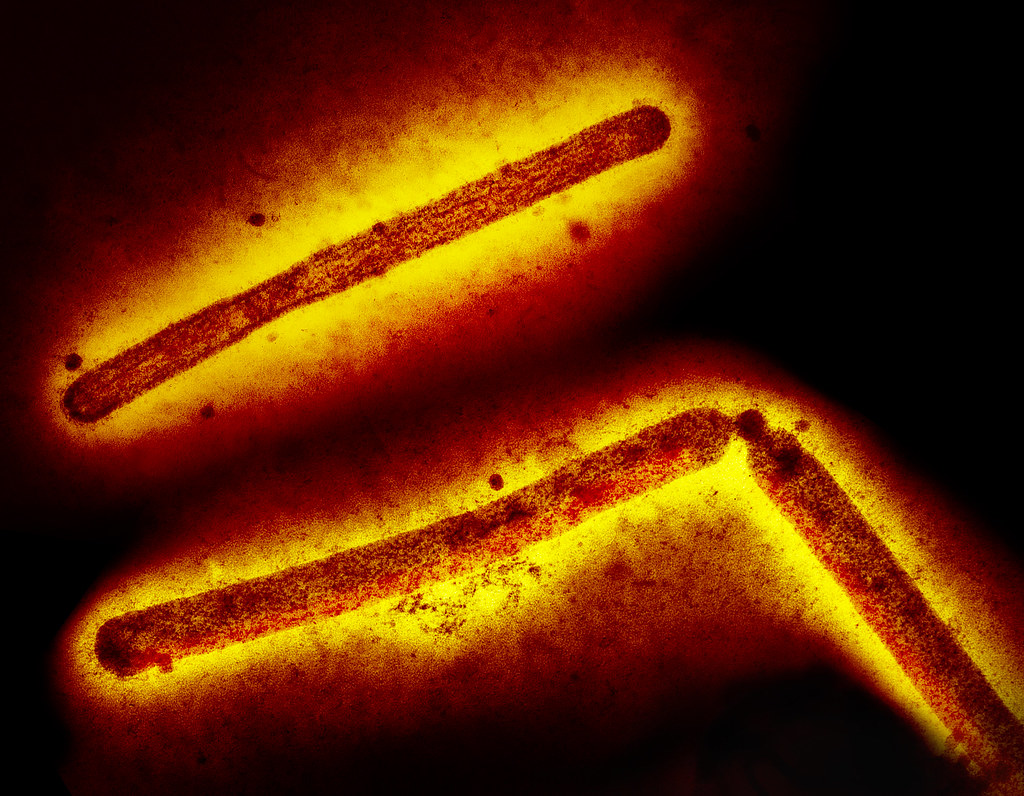

Estes dois focos são do subtipo H5N1, que tem sido o mais comum no país.